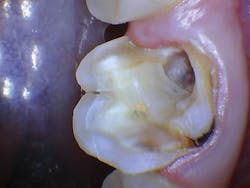

The patient was anesthetized with 1.7 ml of 4% articaine with epinephrine 1:100,000. The entire procedure was performed using the "Hard and Soft Tissue" setting. The gingiva was flapped to expose bone using the 0.25 mm spot size with 1% mist and cutting speed between 20% and 50% (figures 9-10). Only 0.5 mm of tooth structure was coronal to the alveolar bone. The osseous tissue was removed to establish biologic width and expose tooth structure coronal to bone for a proper restoration (figure 11). Proper positive bony architecture was maintained. The 0.75 mm spot size was used with 100% mist and cutting speed between 30% and 60%. A temporary restoration was placed, followed by one suture (figure 12). The total procedure time was 50 minutes. The patient was reevaluated after seven days (figure 13), and the final crown was placed (figure 14).

Figure 11: Flapped, postosseous reduction

Figure 12: Immediate post-op